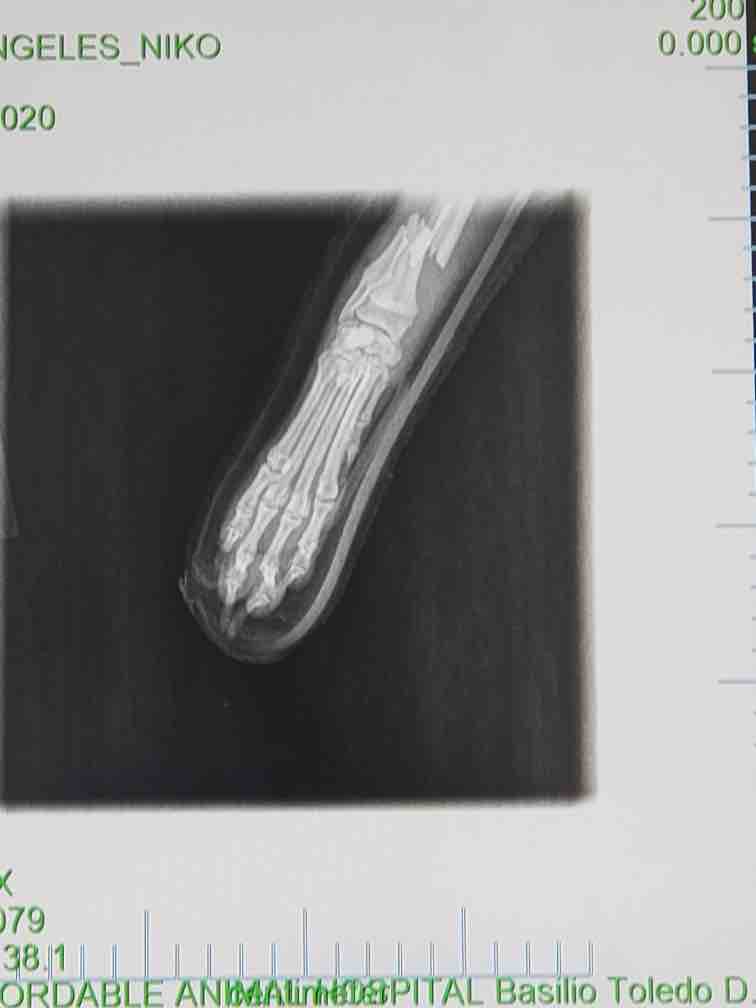

Hello, we are asking for the help of our family and friends to help our beloved dog Niko get the care that he needs. On March 16, 2021, our dog Niko suffered a very bad accident, which left his right front leg broken. We took Niko to our Local Emergency Pet Hospital where we were told that Niko had broken his Radius and Ulna in many places and that he would require surgery to try and save his leg. As you all know, pet Hospital bills are always very expensive and due to the pandemic these extra costs cause an even greater financial burden on any family. We love our Niko and want nothing but to see him get better. We were given very few options of how to go forward with his accident. The options were surgery with aftercare needed, Amputation, or to put to our baby Niko to sleep. Our Niko is such a great and loving dog who we cannot even begin to imagine our lives without him. We want to try anything we can to get Niko back on all fours. Right now more than ever he needs hopes and prayers so that he can get better! We want Niko in our lives so that he may continue to live his happy life here at home with us. We would love and appreciate any help that anyone can donate. Anything will help. No donation is too small. Please help us bring our Niko home.